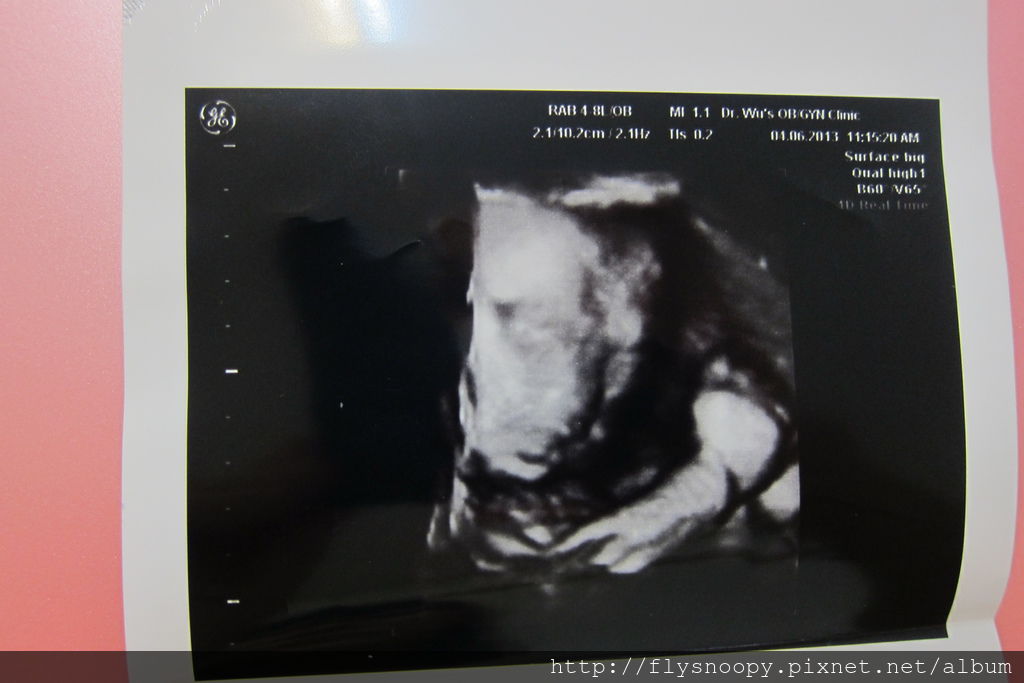

第一張應該是4D,但是還沒有很好看